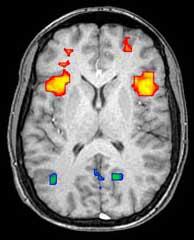

15:20 – جف: مایکل اورت، متخصص مغز و اعصاب در دانشگاه اولم، تغییرات در “شبکه حالت پیشفرض” مغز را مطالعه میکند. اینها قسمتهایی از مغز هستند که وقتی “در حال استراحت” یا “خیالپردازی” هستیم و به چیز خاصی فکر نمیکنیم، فعال هستند. وقتی روی چیز خاصی تمرکز میکنیم، این مناطق مغزی معمولاً آرام میشوند. در مغز حاملان جهش HD، این ساکت شدن ناقص است، به دلایلی که هنوز مشخص نیست. دانشمندانی مانند مایکل اورت از تکنیکی به نام “تصویربرداری تشدید مغناطیسی عملکردی” یا fMRI برای مطالعه اینکه کدام قسمتهای مغز در یک زمان معین فعال هستند، استفاده میکنند.

15:27 – اد: نلی جورجیو-کاریستیانیس (استرالیا) نیز در مورد فعالیت مغز صحبت میکند. دکتر G-K از تستهای تفکر در اسکنر MRI عملکردی برای به چالش کشیدن و بررسی عملکرد مغز در حاملان جهش بیماری هانتینگتون استفاده میکند. او به طور مکرر از fMRI در طول زمان استفاده میکند، ما میتوانیم ببینیم چه تغییراتی در HD رخ میدهد و چه چیزی را میتوانیم اندازهگیری کنیم و هدف ما نجات با درمان است.